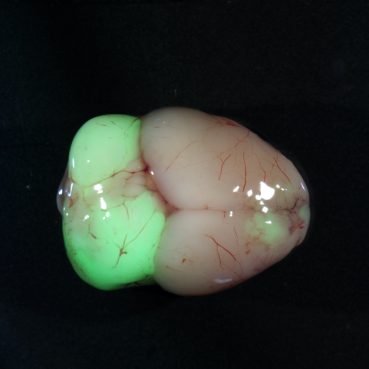

Medulloblastoma primary tumor in the cerebellum of a Sleeping Beauty Patched1 Het mouse model